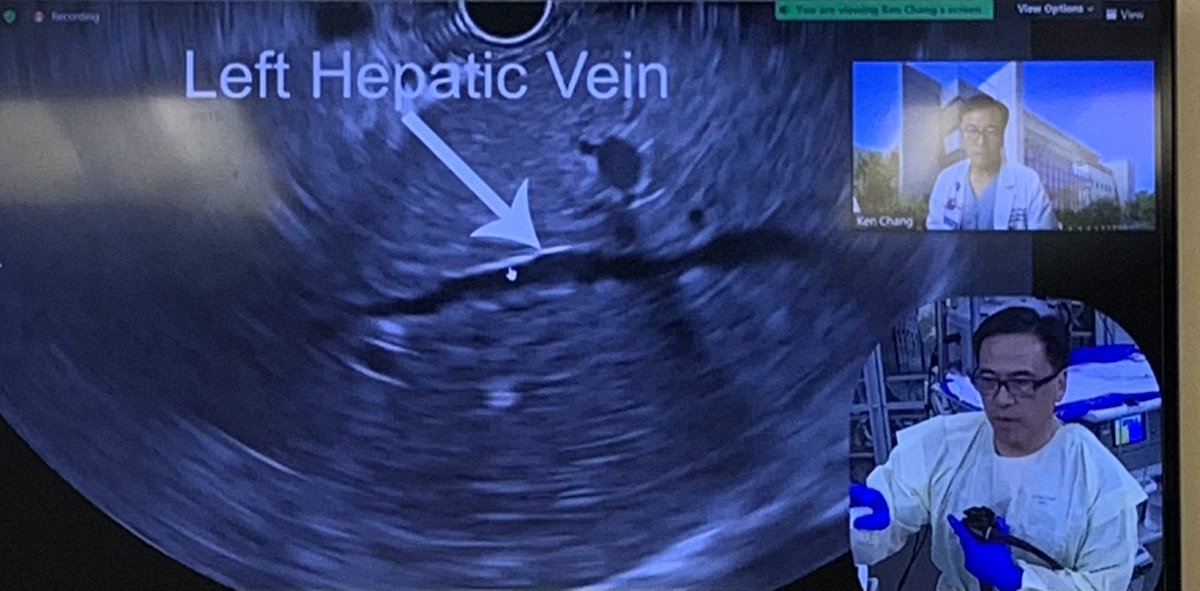

#ScopingSundays Susan Lou Dalbir Sandhu, MD, FACG, FASGE Mohammad Bilal, MD Ahmad Bazarbashi MD أحمد بازارباشي Roberto Simons-Linares, MD Vaibhav Wadhwa Ramzi Mulki, MD Sergio A. Sánchez-Luna, MD, DABOM (He/Him/His) Lizzie Aby, MD Malorie Simons Nneka N. Ufere, MD MSCE Jacqueline N. Chu, MD Here is a nice algorithm on how to manage different polyps!